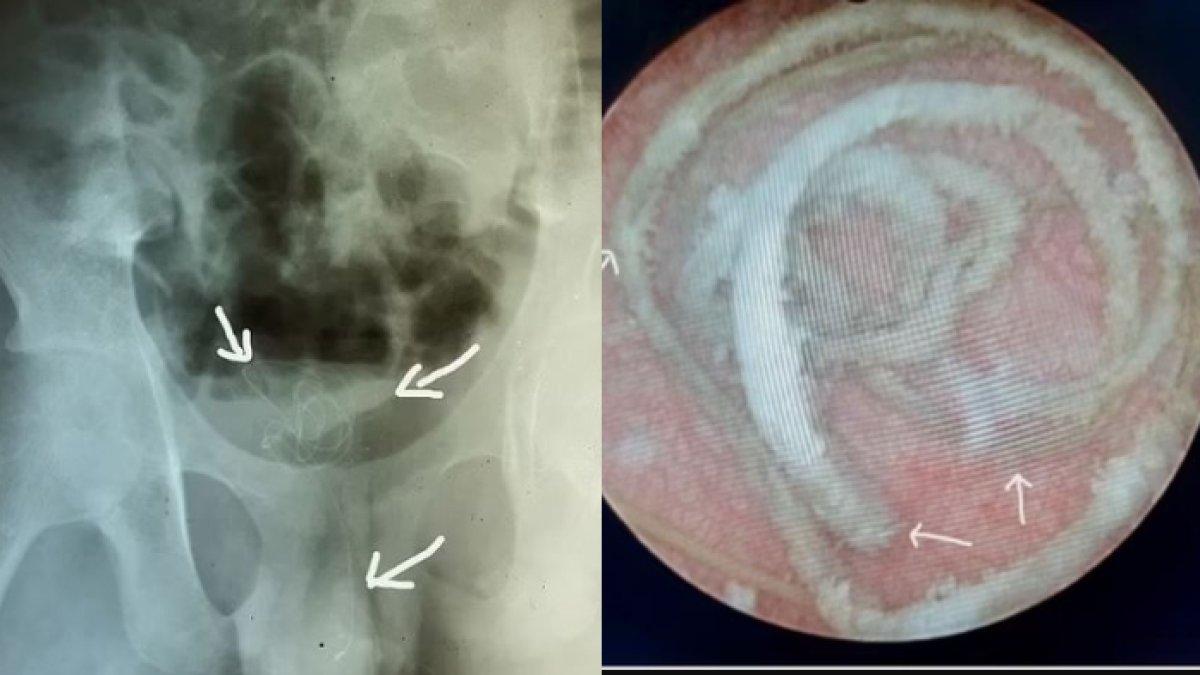

Para dokter di rumah sakit di Kolombo, Sri Lanka menemukan sesuatu melingkar yang tidak diketahui di perut pasien melalui pemindaian ultrasonografi.

Mereka melakukan prosedur cepat yang disebut sistoskopi.

Yakni memasukkan tabung dengan lampu dan kamera di ujungnya ke dalam uretra untuk melihat ke dalam kandung kemih.

Mereka mendapatkan gambaran kawat bertatahkan garam kalsium di kandung kemih, kemudian dokter melakukan pembedahan.